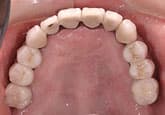

MJさん(20歳・女性)

初診時:左上の歯肉が痛い

初診時

3週間後

さらに正しいはみがき

を行って3週間後

ここまで患者さんが丁寧に歯をみがいただけです。

歯科医と衛生士は何もしていません。

さらに3週間後

歯石除去

歯石が見えてきたので、歯石を除去しました。

健康な歯肉に回復しました。